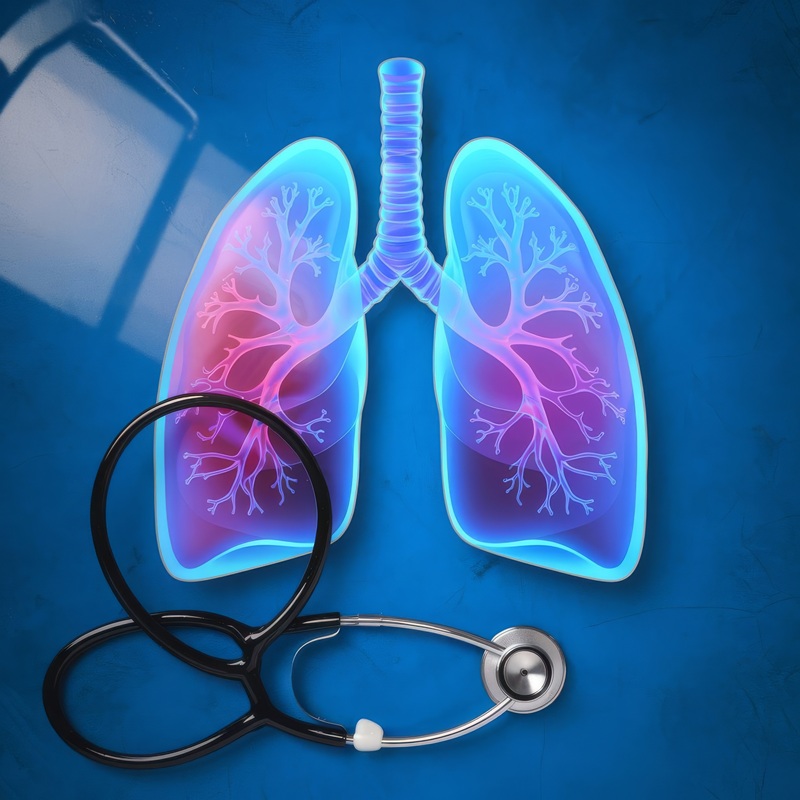

El Dr. Eduardo León Guadarrama brinda atención especializada en neumología enfocada en el diagnóstico, tratamiento y seguimiento de enfermedades respiratorias. Su enfoque médico se basa en una evaluación clínica integral apoyada por estudios avanzados como espirometría, broncoscopia, ultrasonido pulmonar y otras pruebas diagnósticas que permiten valorar la función pulmonar con precisión. A través de una atención personalizada, el Dr. Eduardo León Guadarrama busca mejorar la calidad de vida de sus pacientes mediante un diagnóstico oportuno y tratamientos adecuados para diferentes padecimientos respiratorios dentro de Neumología en CDMX y Edo. Mex.